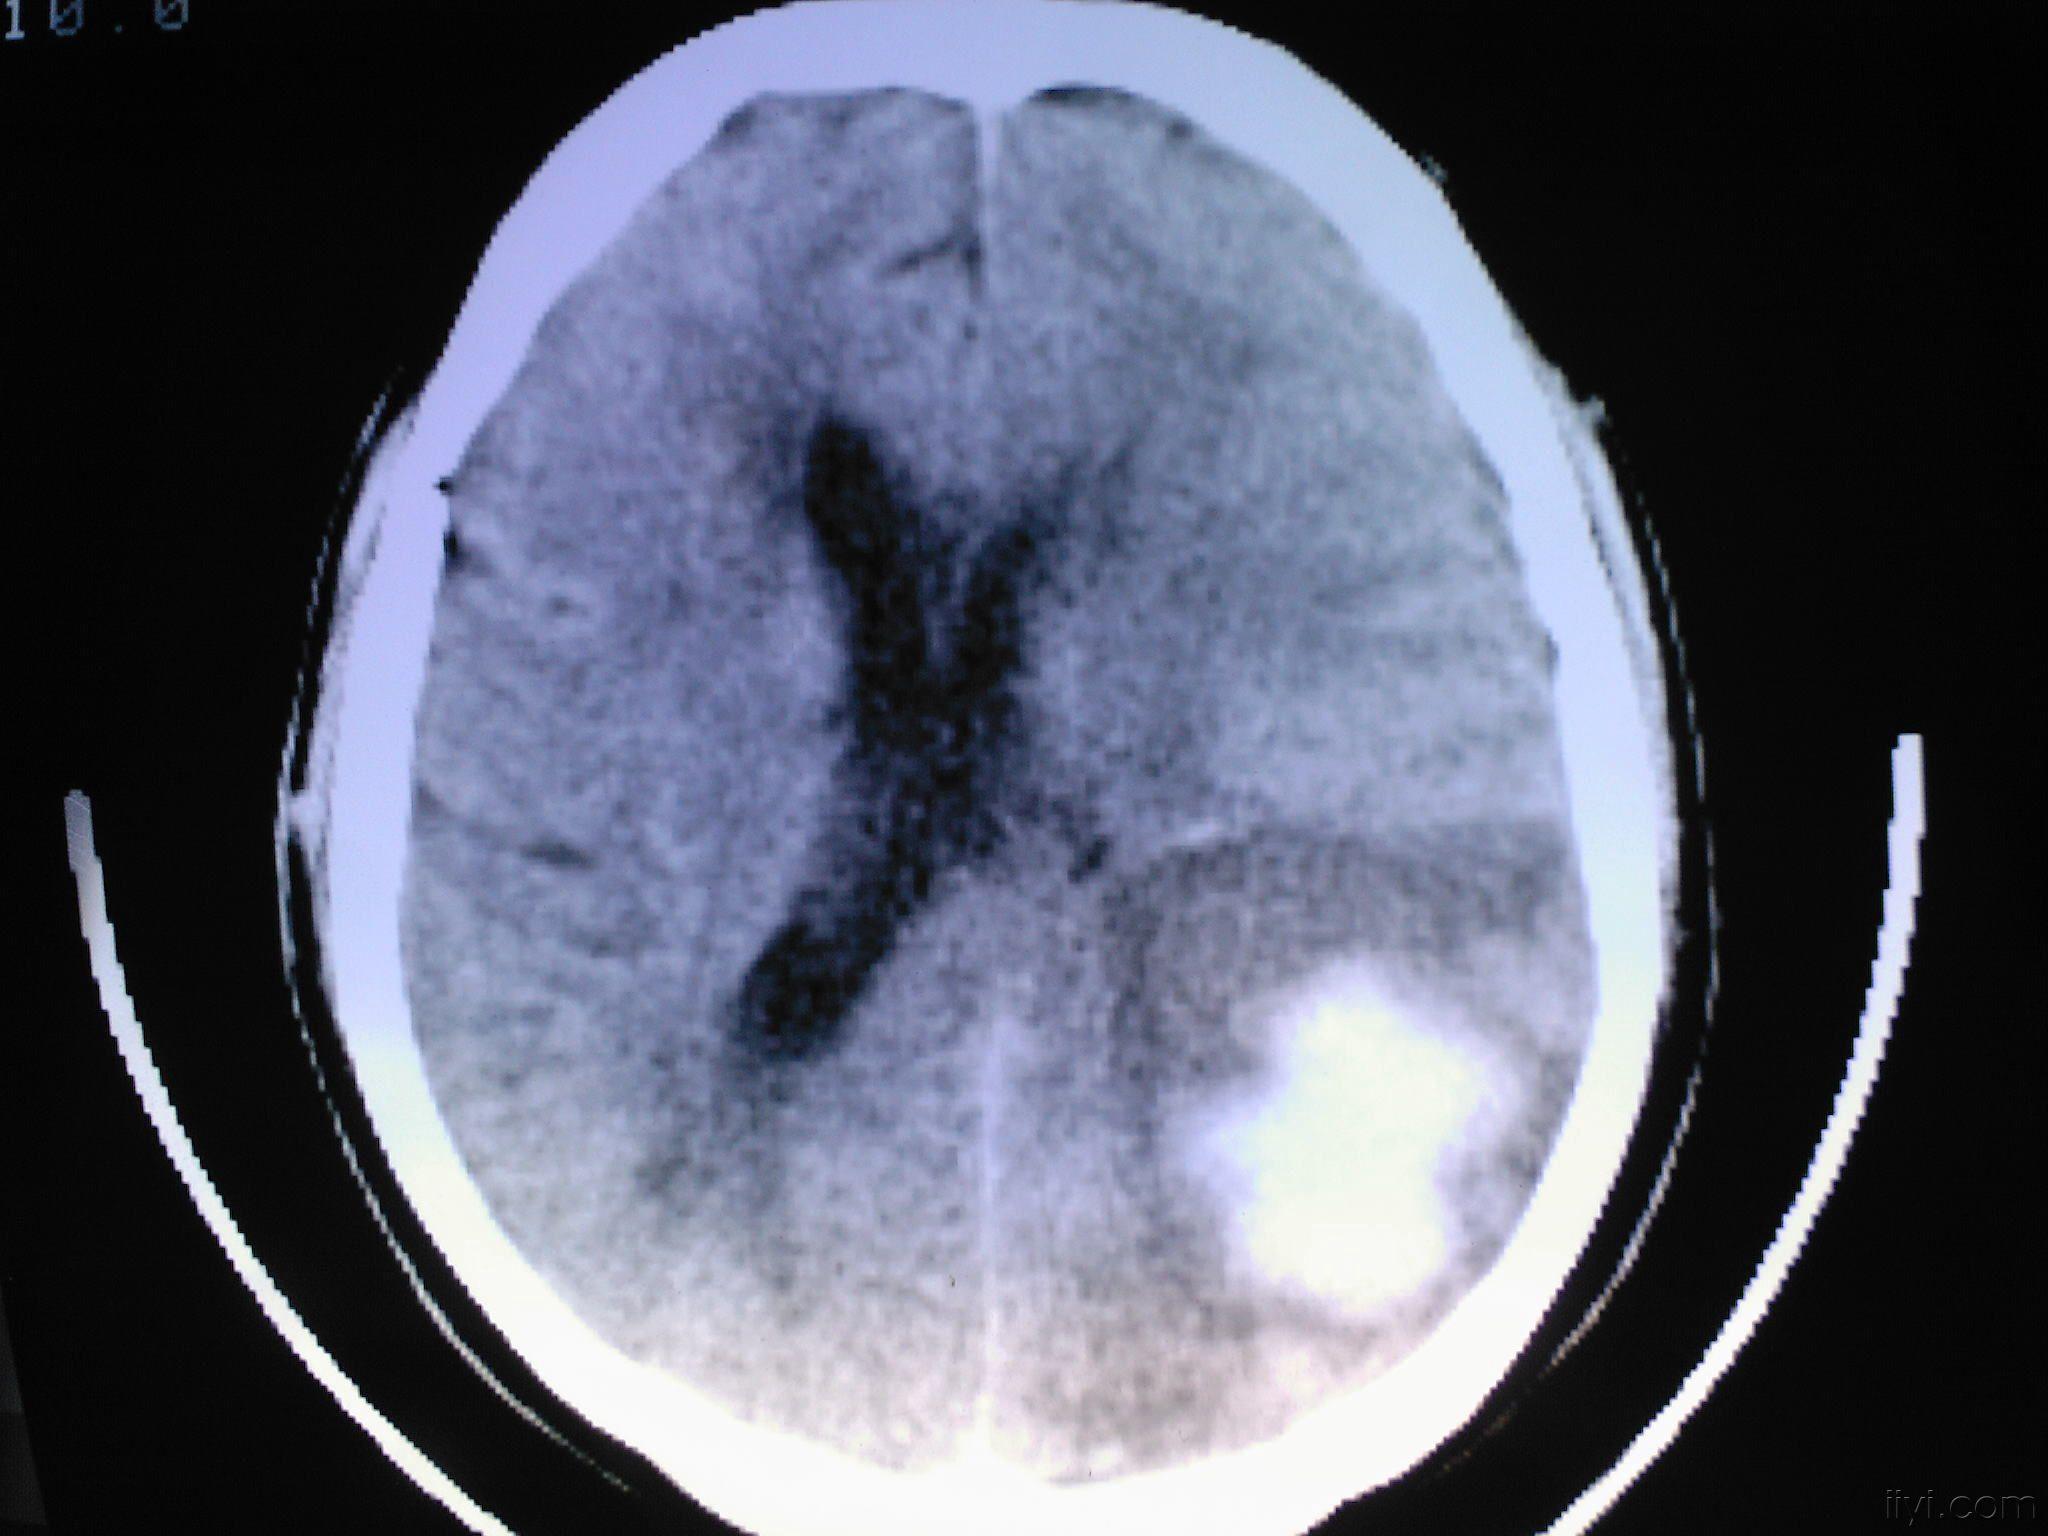

脑出血图片

脑出血